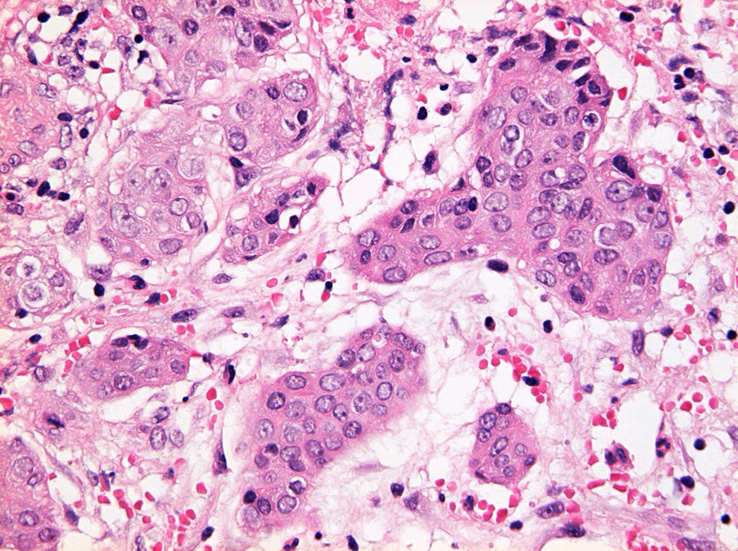

S状結腸粘膜生検組織所見:

粘膜筋板直下に小型胞巣を作って浸潤し炎症性の間質をともなう。 浸潤性増殖のわりに細胞は均一, そんなに異型性も強くない。apoptosisに陥った細胞が散在する。部位によっては胞巣状増殖細胞は細胞間橋がありそうな扁平上皮様に見える。深いところは線維性間質が増えてきて細胞は索状となりcarcinoidなども鑑別候補となるかもしれない。明らかな腺管形成, 粘液産生はみられない。35歳男性, わりとおとなしい扁平上皮癌様の組織か?と生検初見時に考えられた。desmoplasticな間質にもよく観察するとバラけた細胞異型が認められる。 (腫瘍胞巣①, ③)